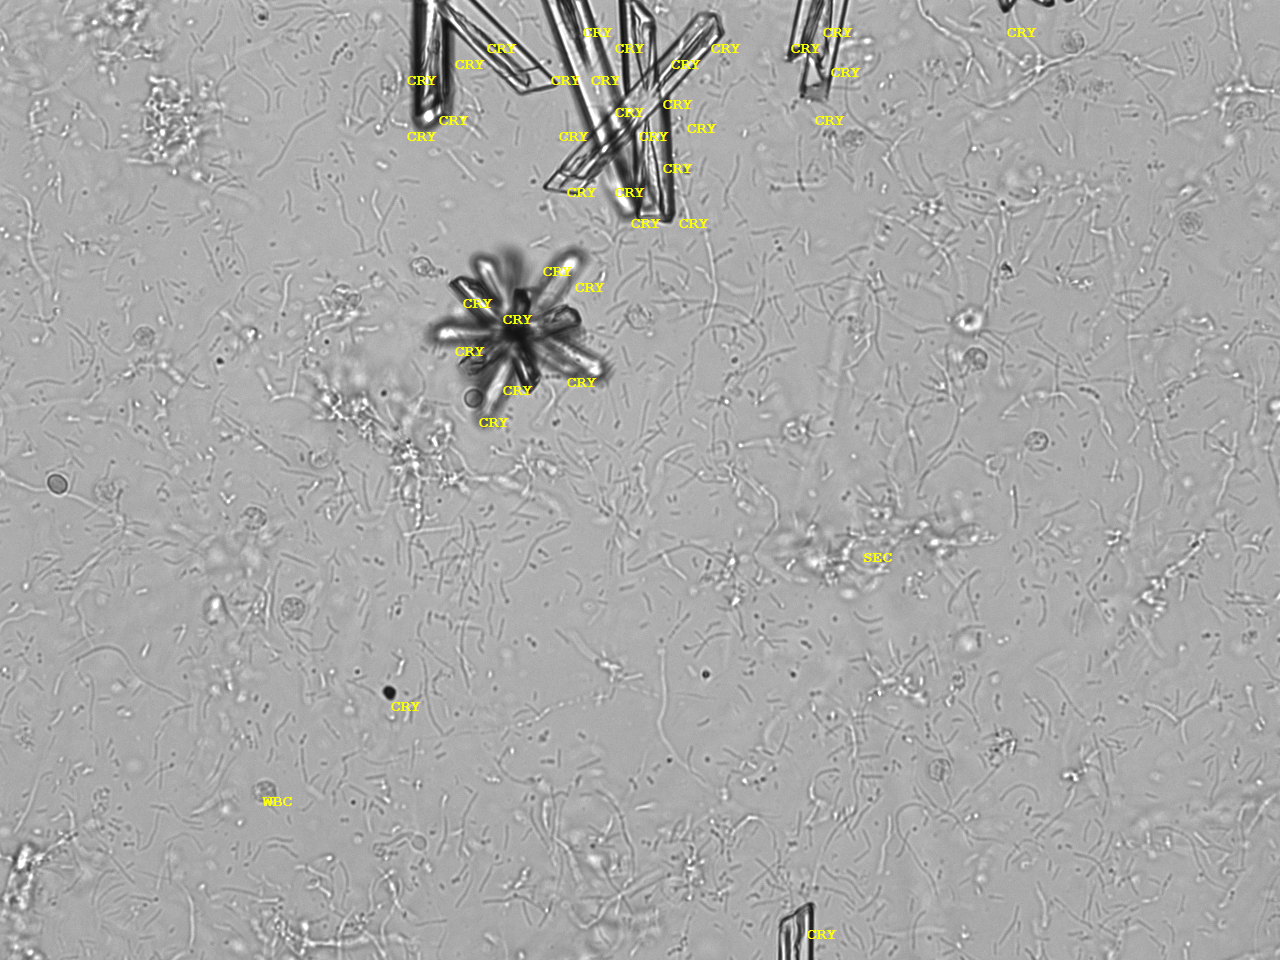

Urin-Feature: CaPhosphate